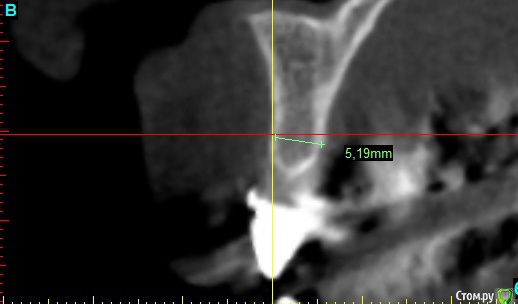

x4ex Опубликовано 16 октября, 2017 Автор Поделиться Опубликовано 16 октября, 2017 Графта не было. Насчёт удаления зуба не помню, возможно даже там первичная адентия была.Девушке 27лет и она пришла с коронкой на 12 с консолью на 11. КТ до есть, после только прицельный. Завтра всё добавлю. Имплант ставил субкрестально, примерно на 2мм, исходя из положения зенита соседнего зуба. Ссылка на комментарий

x4ex Опубликовано 17 октября, 2017 Автор Поделиться Опубликовано 17 октября, 2017 Подозрительно не то слово. Клянётся, что проходит каждый год медосмотры и никаких патологий выявлено не было.Не знаю, как изменить шапку, поэтому добавлю снимки сюда. Ссылка на комментарий

Большой Зеленый Опубликовано 17 октября, 2017 Поделиться Опубликовано 17 октября, 2017 Глубоко поставил . Возможно плохо пришил ССТ. Ссылка на комментарий

x4ex Опубликовано 17 октября, 2017 Автор Поделиться Опубликовано 17 октября, 2017 Глубоко поставил . Возможно плохо пришил ССТ.Там от платформы до зенита как раз 3 мм - на последнем снимке виден край времянки. Ну ладно, пусть глубоко, но разве от этого может быть абсцесс? Ссылка на комментарий